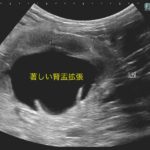

急性腎機能障害の猫ちゃんが(BUN>130mg/dl、Cre>14mg/dl、高カリウム血症)治療のため救急で対応しました。無麻酔CTでは両側に尿管結石が確認されました。著しく拡張している左腎の腎盂に一時的な腎瘻カテーテルを設置し、尿の排泄路の確保を行います。しかし、腎数値に改善は見られませんでした。腎盂造影を行うと拡張している腎臓において尿の産生と排泄は行われている様です。一方、腎盂拡張のほとんどない右腎の腎盂造影では尿の排泄が確認されません。今回の急性腎機能障害の原因は機能の残っていた右腎の急性尿管閉塞による急性腎障害と診断しました。左腎に関しては尿の産生はあるものの慢性腎機能障害であり、すでに尿濃縮能は失われていると判断しました。右腎の問題に対して尿管膀新吻合短尺型ステント設置術を行いました。術後は徐々に腎数値は低下し、腎機能の回復が得られました。一見すると腎盂拡張の顕著な側が急性腎障害の責任病変と判断しがちですが、片腎が十分に機能していれば腎数値に影響はほとんどなく、どちらの腎臓を治療対象とするか?エコー、CTなどの画像診断、血液検査、一時的な腎瘻カテーテルの設置、腎盂造影など総合的な判断が必要です。また判断がつかず、左右同時に治療が必要な場合もあります。